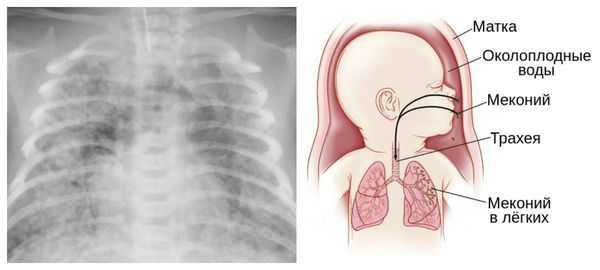

Из-за снижения кровотока в почках плода выделение мочи значительно уменьшается, развивается маловодие. Также изменяется характер околоплодных вод: они теряют прозрачность, становятся мутными, приобретают желтоватый или зеленоватый оттенок из-за примеси мекония — первых фекалий ребёнка.

Осложнения перенашивания беременности

Для плода большую опасность представляет асфиксия (острая гипоксия) и отслойка плаценты. Нехватка кислорода внутри утробы стимулирует плод выполнить несвоевременные дыхательных движения. Они приводят к заглатыванию вод и возможному воспалению лёгочной ткани — пневмониту. Если в водах есть примесь мекония (первородного кала), то велика вероятность мекониальной аспирации — проникновения содержимого кишечника новорождённого в его лёгкие.